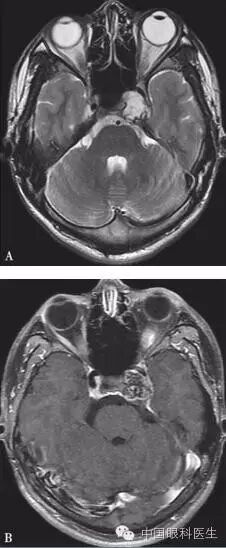

体格检查:双眼矫正视力0.8。右眼眼睑位置及眼球运动均正常,左眼上睑下垂,遮盖瞳孔上半部分,提上睑肌肌力4mm,左眼不能外展,上转、下转、内收运动均部分受限。患者右眼瞳孔直径3mm,左眼4mm;右眼对光反射灵敏,左眼迟钝,RAPD(-)。双眼眼底、眼压均正常。视觉诱发电位(visual evoked potential,VEP)、视野检查均未见明显异常。头颅MRI平扫+增强结果显示,左侧鞍旁海绵窦内T1WI稍低信号、T2WI稍高信号影,大小为21mm×23mm×22mm,增强扫描病灶呈不均匀强化,内可见多发的未强化区,左侧颈动脉海绵窦段受压外移,但结构未见明显损害(图2-3-0-1)。头颅CT平扫显示左侧鞍旁密度减低影,CT值为21Hu,大小为2.3cm,边缘可见钙化影,双侧眶内和球后未见异常(图2-3-0-2)。患者转入神经外科并行经额颞颧弓硬膜外入路左侧海绵窦区占位性病变切除术。术中快速冰冻切片病理学检查示,切除的组织标本富含黏液,制片困难。术后病理报告:左侧海绵窦区软骨源性肿瘤。考虑软骨瘤可能性大,局部细胞生长活跃,细胞间质伴黏液变性,免疫组织化学染色显示,肿瘤细胞对S-100和CK均呈阴性反应(图2-3-0-3)。术后患者左眼视力下降,额部及颊部皮肤感觉迟钝。眼科检查:右眼检查同术前,左眼矫正视力0.5,角膜上皮粗糙,角膜荧光素染色弥漫性着色,RAPD(-)。检眼镜检查示视盘界清,色红,视网膜血管走行正常,黄斑区未见明显异常。VEP、视野检查均未见明显异常。给予玻璃酸钠滴眼液点左眼、重组牛碱性成纤维细胞生长因子软膏涂左眼结膜囊并给予营养神经、改善全身血液循环药物治疗1周后,检查示见角膜上皮透明,角膜荧光素染色不明显,矫正视力0.8,左眼提上睑肌肌力测试可上提10mm。术后1个月复诊见,上睑下垂治愈,眼球运动受限明显好转。

注:A. T2WI;B.增强扫描。左侧鞍旁海绵窦内可见T1WI稍低信号、T2WI稍高信号影,大小约为21mm×23mm×22mm,增强扫描病灶呈不均匀强化,其内可见多发未强化区,左侧颈动脉海绵窦段受压外移,未见明显侵犯